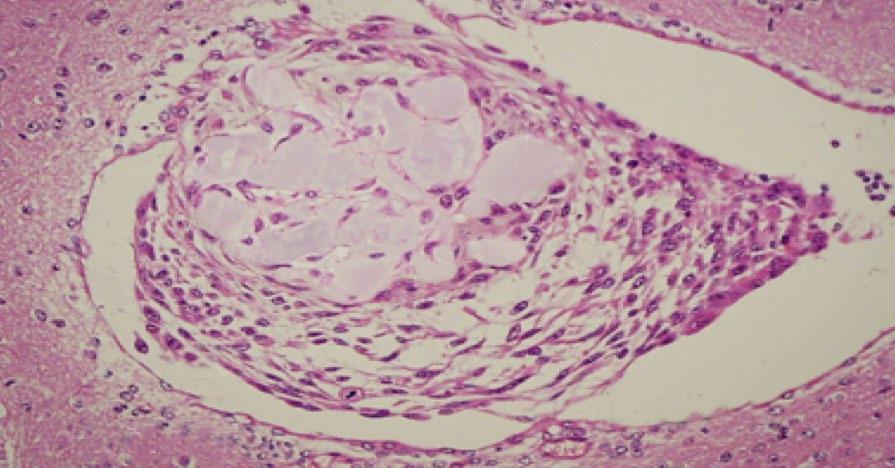

STIMULATING BLOOD VESSEL FORMATION WITH MAGNETS

A magnetic field could boost blood vessel growth to regenerate damaged tissues.

A magnetic field can be used to stimulate blood vessel growth, according to a study published in the journal Science and Technology of Advanced Materials. The findings, by researchers at the Técnico Lisboa and NOVA School of Science and Technology in Portugal, could lead to new treatments for cancers and help regenerate tissues that have lost their blood supply.

“Researchers have found it challenging to develop functional, vascularized tissue that can be implanted or used to regenerate damaged blood vessels,” says Frederico Ferreira, a bioengineer at Técnico Lisboa’s Institute for Biosciences and Bioengineering. “We developed a promising cell therapy alternative that can non-invasively stimulate blood vessel formation or regeneration through the application of an external low-intensity magnetic field.”

The researchers worked with human mesenchymal stromal cells from bone

marrow. These cells can change into different cell types, and also secrete a protein called VEGF-A that stimulates blood vessel formation.

The research team, including Ana Carina Manjua, Frederico Ferreira, and Carla Portugal, developed two hydrogel supports made of polyvinyl alcohol (PVA) and gelatin, both containing iron oxide nanoparticles. Cells were then cultured on the hydrogels and exposed to a low-intensity magnetic field for 24 hours.

The cells on the PVA hydrogel produced less VEGF-A after the magnetic treatment. But the cells on the gelatin hydrogel produced more. Subsequent lab tests showed that these VEGF-A -rich extracts improved the ability of human vascular endothelial cells to sprout into branching blood vessel networks.

Endothelial cells were then placed onto a culture dish with a gap separating them. The conditioned media from magnet-treated mesenchymal stromal cells

from the gelatin hydrogel was added to the endothelial cells, which then moved to close the gap between them in 20 hours. This was significantly faster than the 30 hours they needed when they had not received magnetic treatment. Placing a magnet directly below the dish triggered the mesenchymal stromal cells to close the gap even faster, in just four hours.

More work is needed to understand what happens at the molecular level when a magnetic field is applied to the cells. But the researchers say gelatin hydrogels containing iron oxide nanoparticles and mesenchymal stromal cells could one day be applied to damaged blood vessels and then exposed to a short magnetic treatment to heal them.

The team suggests that magnet-treated cells on PVA, which produce less of the growth factor, could be used to slow down blood vessel growth to limit the expansion of cancer cells.